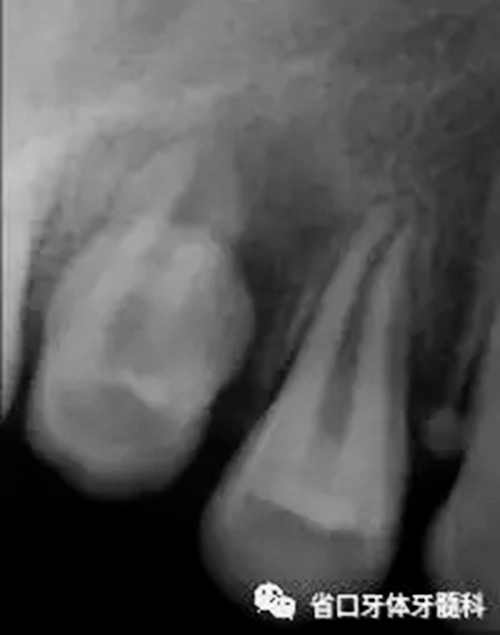

圖2 根尖片(2016-3-19),15未完全萌出,形態(tài)異常, 根尖周和根側(cè)方見低密度影,牙槽骨破壞